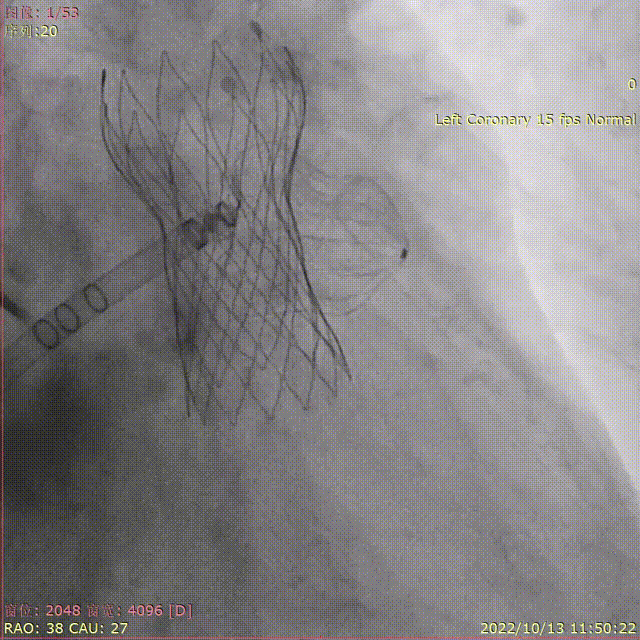

退鞘形成FLX BALL

WATCHMAN FLX™释放